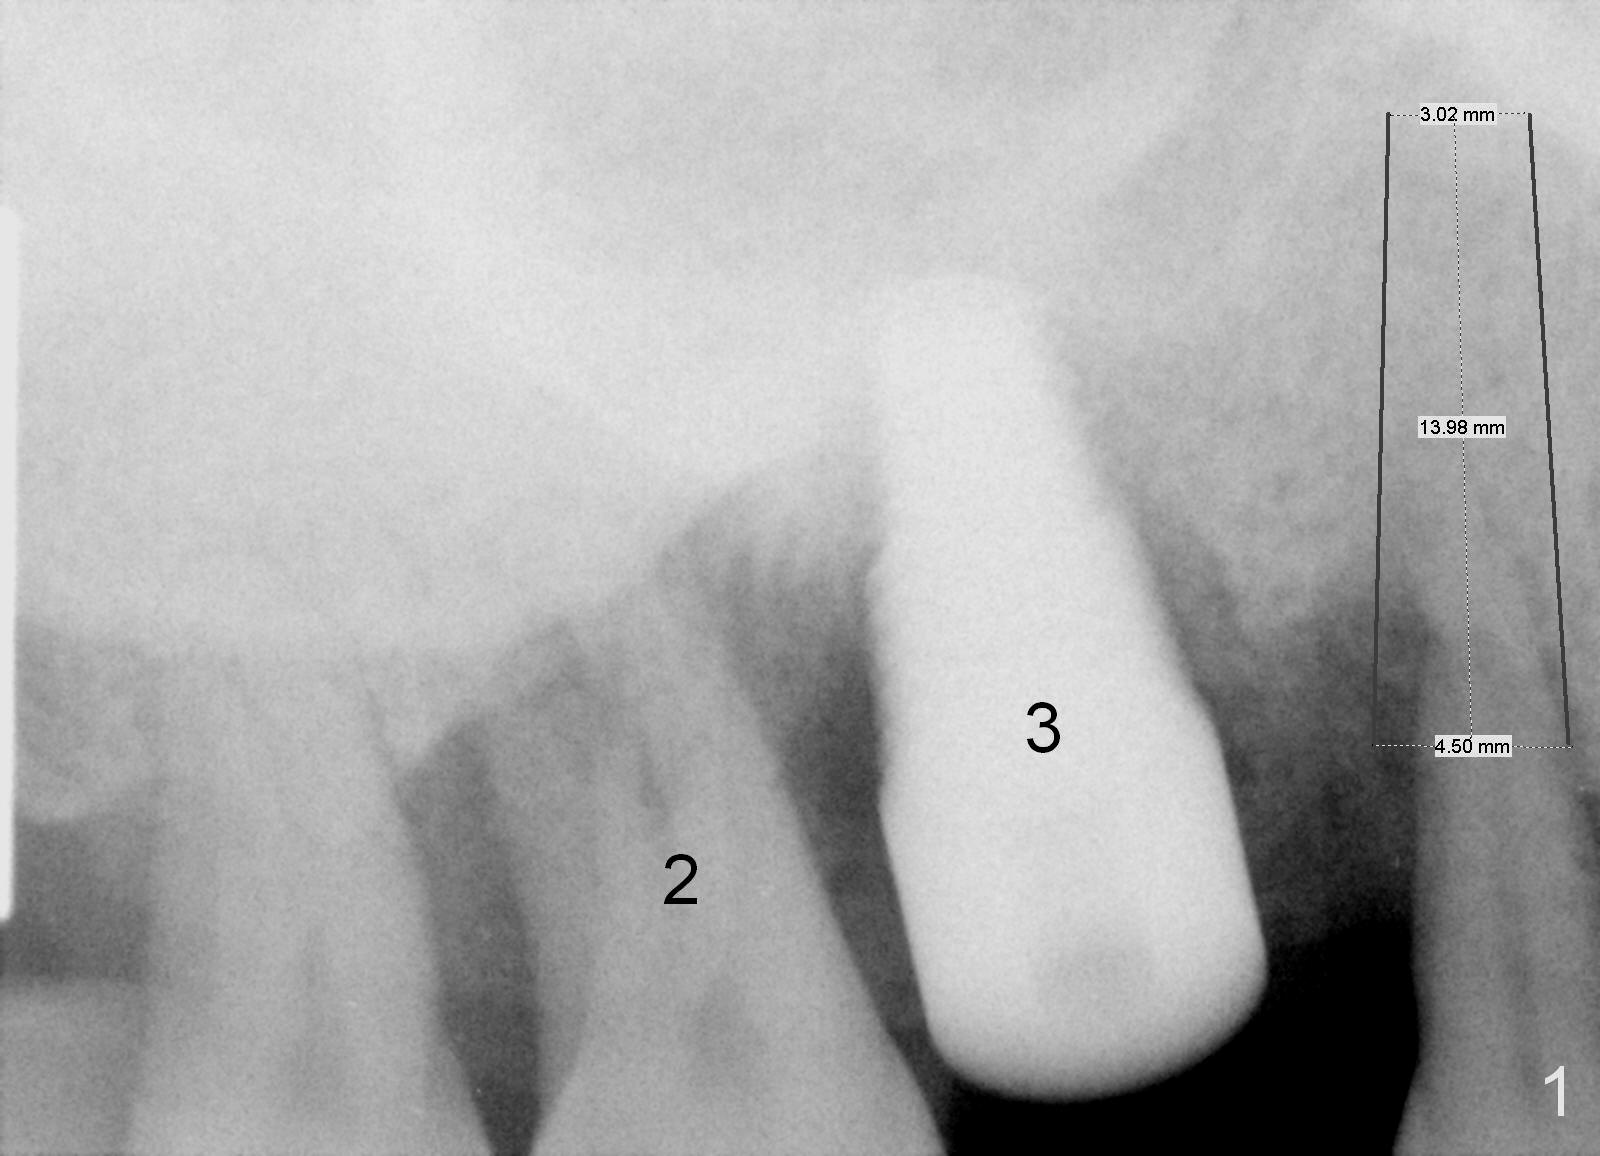

A 46-year-old man has severe chronic periodontitis associated with bruxism. The teeth #3 and 2 have been replaced with immediate implants (Fig.1,2). Now the tooth 4 should be treated in the same manner. Since there is sufficient bone with uneven bone resorption, a long bone-level implant is needed for primary stability (>13 mm). Cuff length of the tissue-level implant is fixed, while there are different lengths of the cuff associated with bone-level implants. Metronidazole is the antibiotic to be used for socket disinfection. Intraop PA should be taken with the pilot drill or a parallel pin to avoid invading the neighboring root or implant. Abundant bone graft is required (circles, Fig.2).